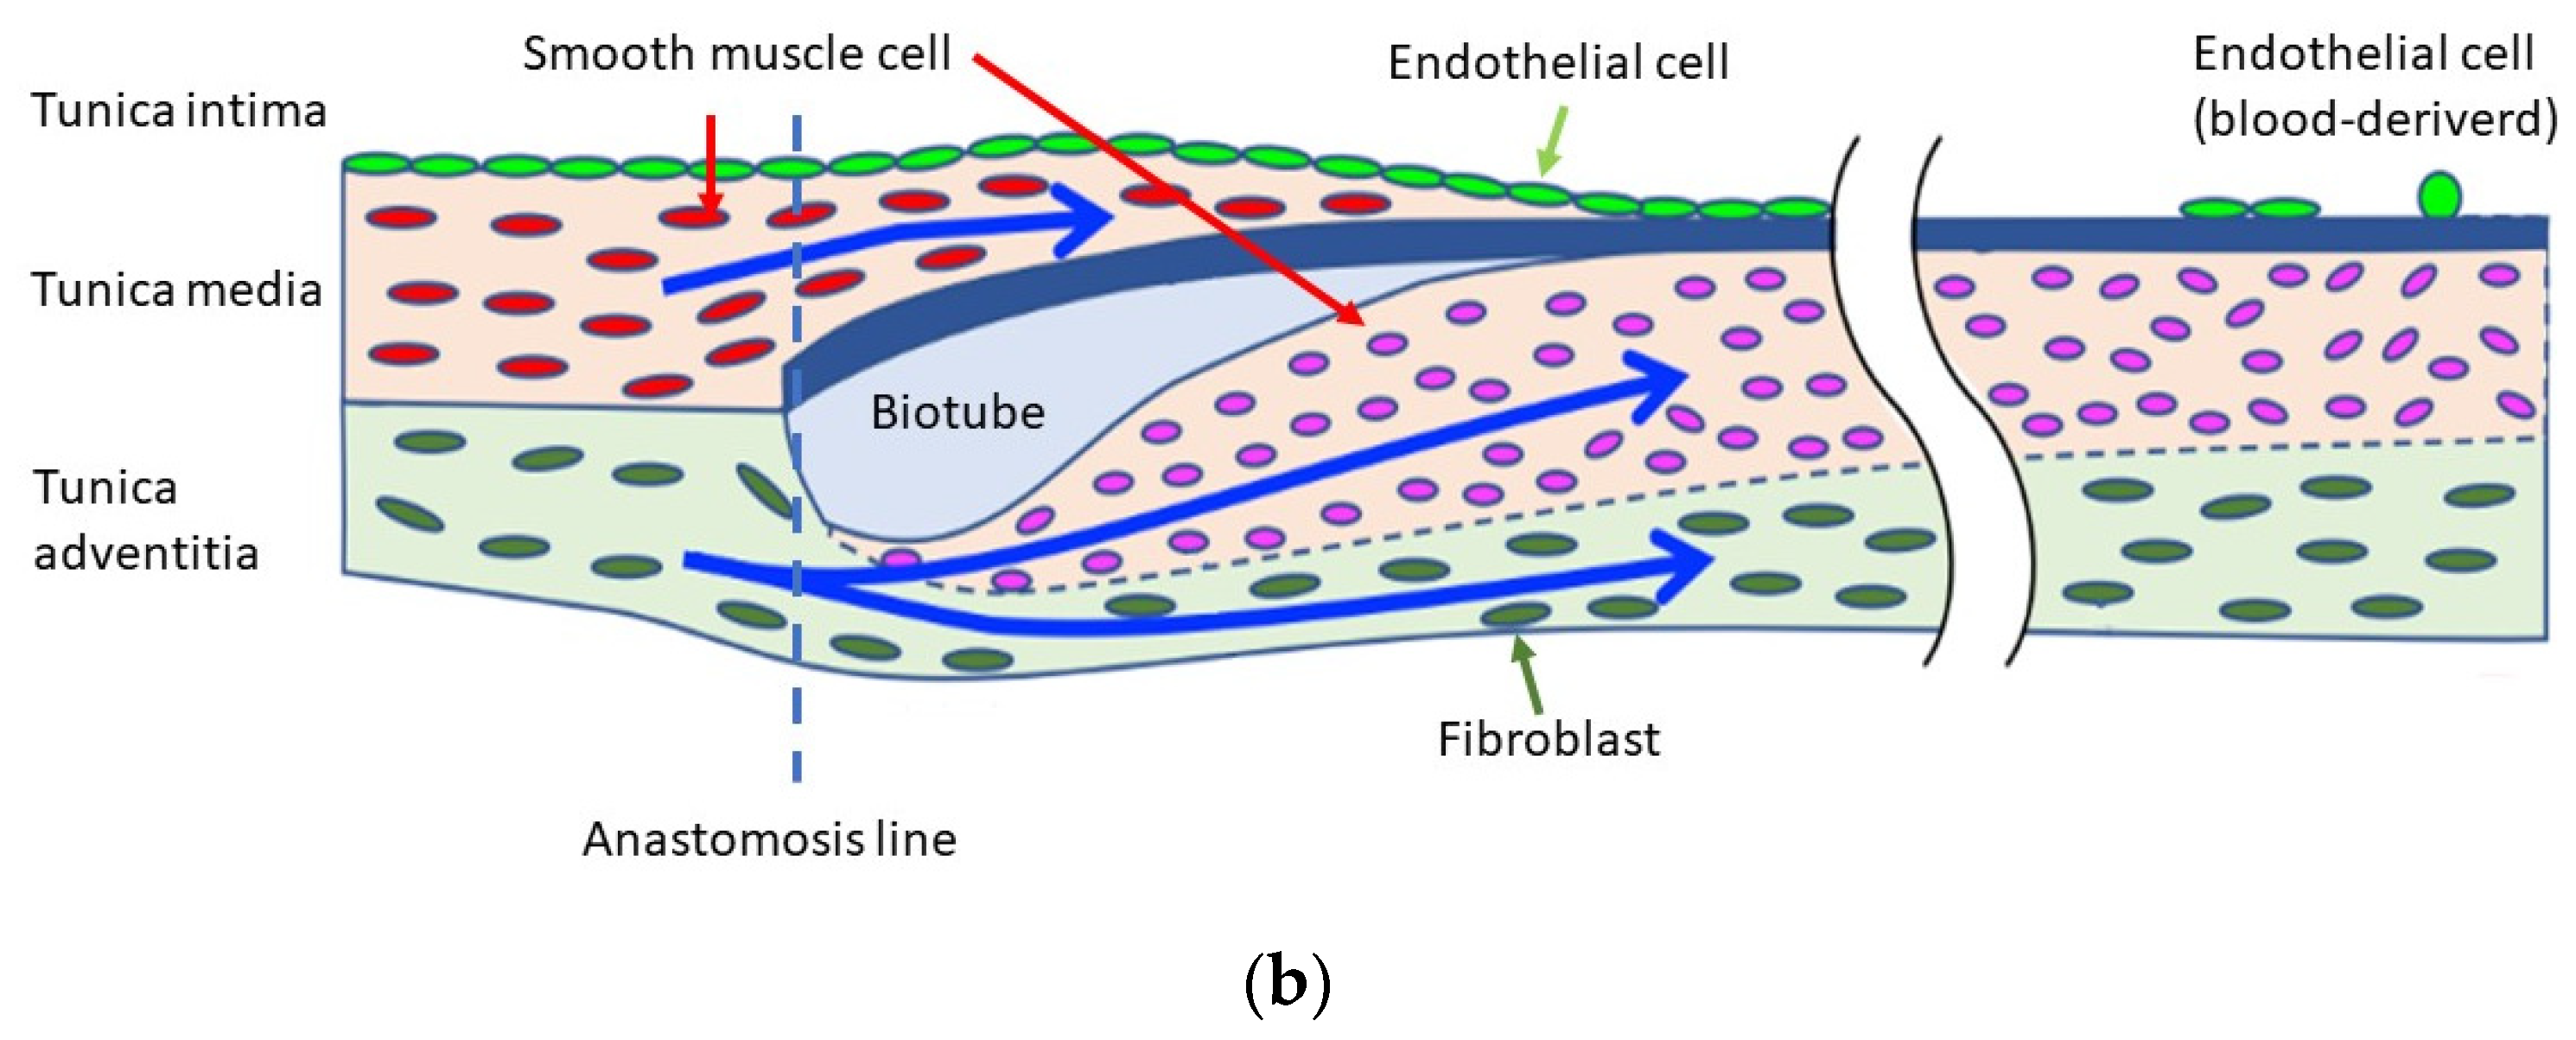

4. Discussion